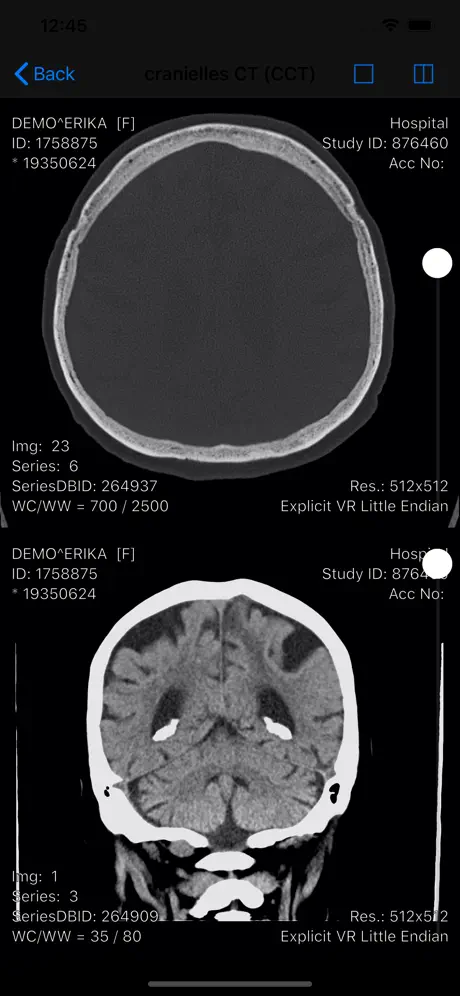

Die RVC Mobile App ist eine native iOS Applikation welche sicher

mit dem einheitlichen RVC Server kommuniziert. Mit dieser App werden iPAD, iPod touch und iPhone zu mobilen Clients die Inhalte aus RVC Clinical PACS / mDMAS intuitiv anzeigen. Dadurch ist ein ortsunabhängiger Zugriff auf das multimediale Archiv möglich. Als Mehrwert dieser Clients wurde auch eine Foto- und Videodokumentation mit integriert, sodass Fotos oder auch Videos direkt vom mobilen Endgerät in das Archiv gespeichert werden können.

- Anzeige von DICOM Objekten

- Vergleichsmodus durch Teilen des Viewports

- Anzeige von DICOM Objekten

Screenshots